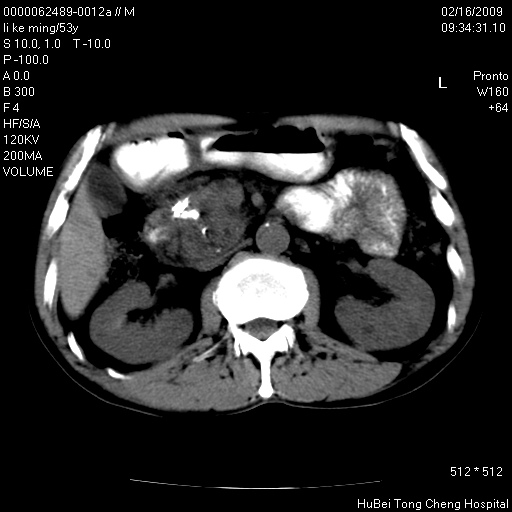

以下是引用卜一在2009-2-16 16:13:00的发言:[br]胰胆管扩张,末端明显狭窄 梗阻,胰头及十二指降段壶腹部结构紊乱。多考虑:十二指降段壶腹部癌!

以下是引用dyqct在2009-2-16 16:58:00的发言:[br]胰头内斑点状及结节状高密度影是钙化灶还是其它?以往做过什么治疗?

以下是引用zsl6918在2009-2-17 8:48:00的发言:[br]符合胰头癌侵犯十二指肠。